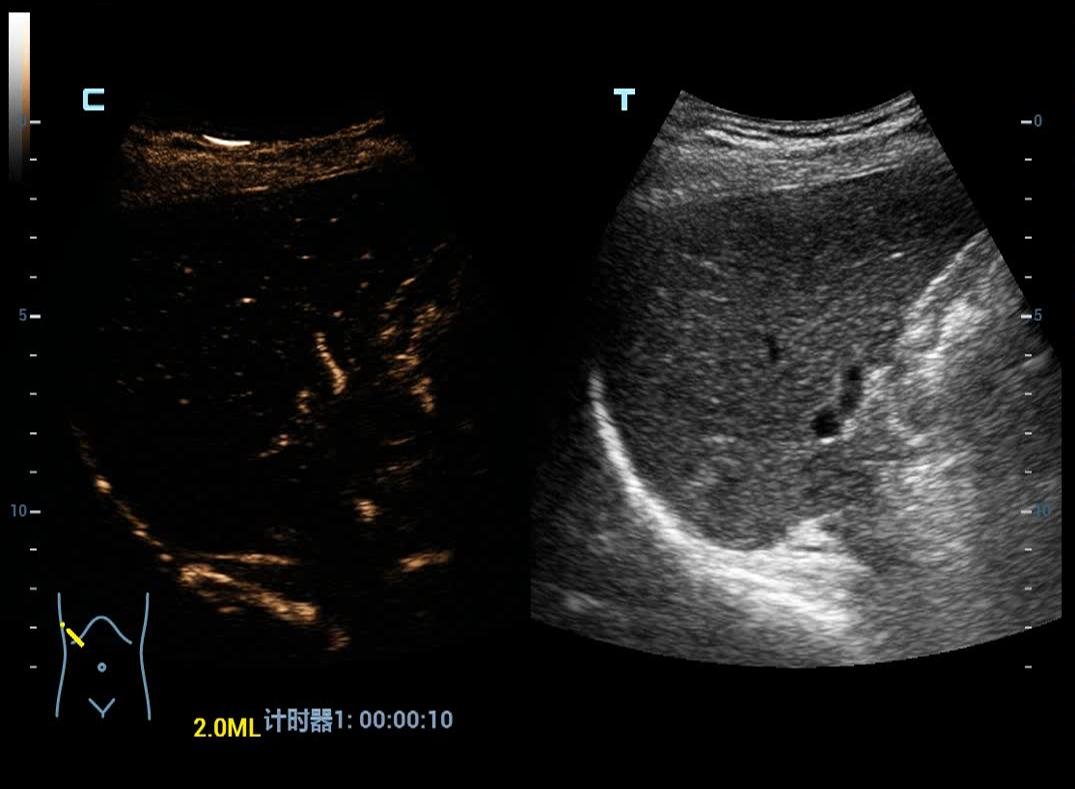

• UWN+ Contrast Imaging (ULTRASOUND CONTRAST IMAGING)

Liver Elastography